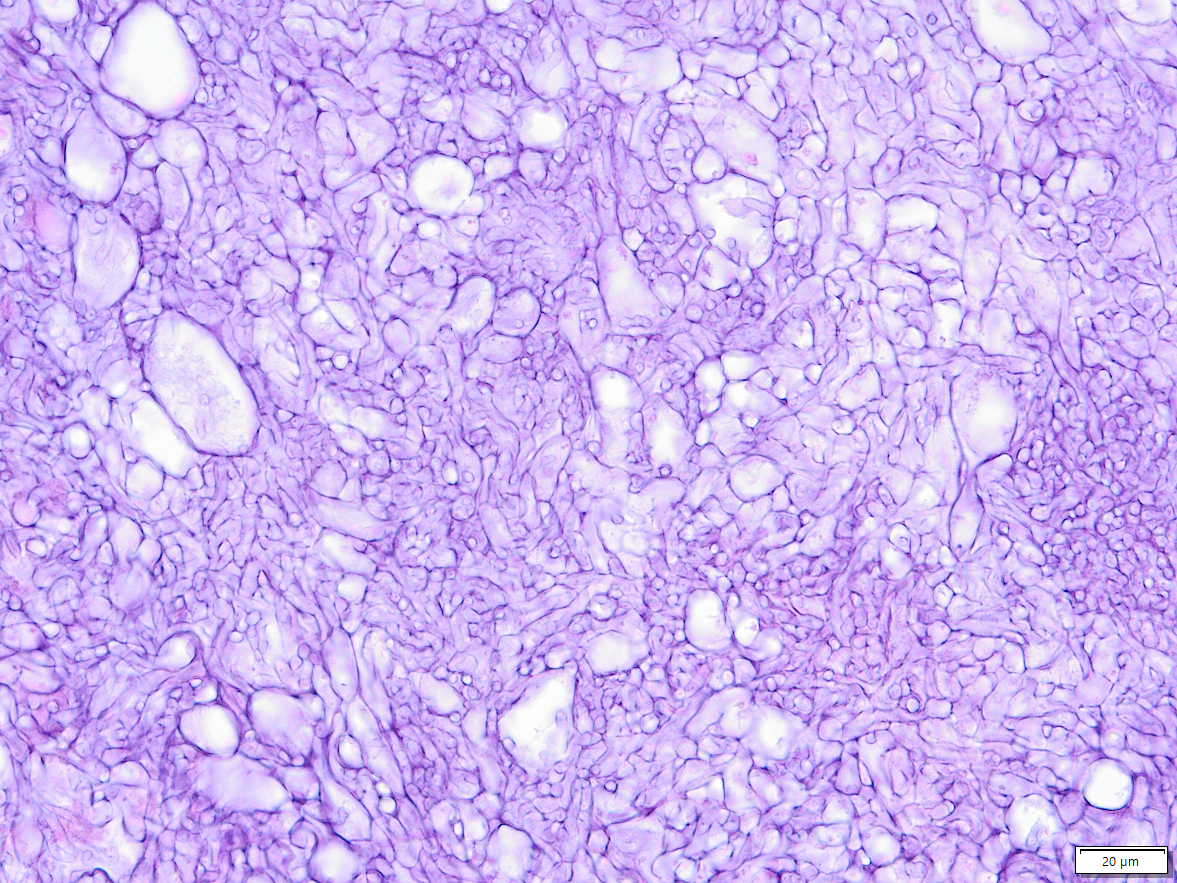

Aspergillose Lunge

Grocott Färbung

Hier besonders, Ausbildung von Konidien, welche sich im Schnitt als kleine Perückenköpfe zeigen.